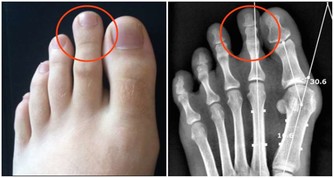

專家表示,千萬不要小看濕疹,若不規範治療,將急癢難耐,逼得患者抓的遍體鱗傷,滲液、乾燥、流血、結痂、粗糙肥厚與裂口,瘙癢變成鑽心的癢,夜裡難以入睡影響日常的生活。而濕疹出現的最常見部位一般在四肢及腰部,尤其以下肢最為明顯。

好發的部位是皮膚油脂分泌最少的小腿前側以及腰部附近。